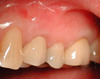

Cas 2